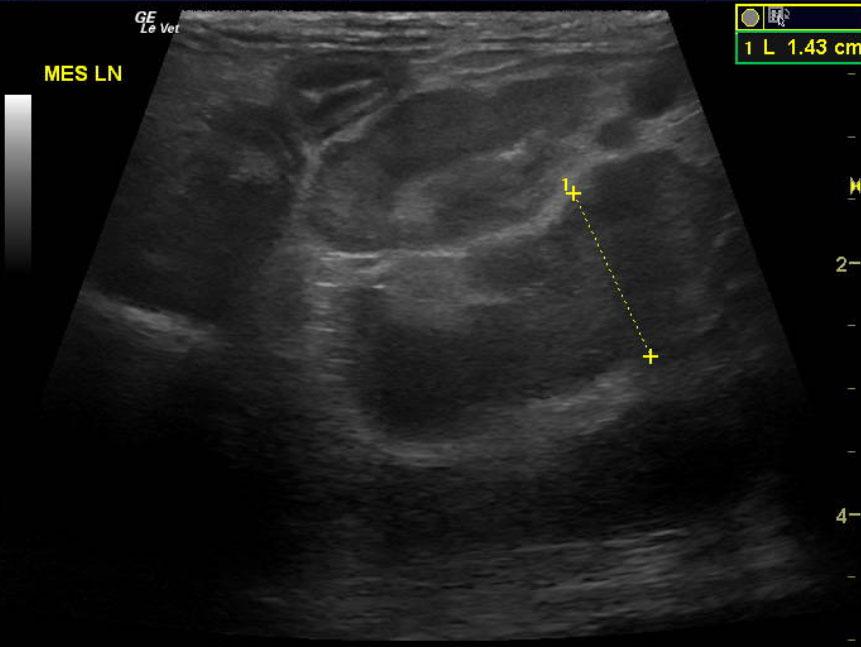

Image Interpretation

The spleen was enlarged and micronodular with slight scalloping contour. The spleen measured 1.33 cm. The mesenteric root lymph nodes were enlarged at 0.62 cm with reactive surrounding fat. Other mesenteric root lymph nodes measured 1.4 x 2.0 cm with reactive fat. Slight free fluid was noted owing to lymphatic strangulation. The remainder of the bowel revealed increased muscularis to mucosa thickening with a 2:1 ratio.